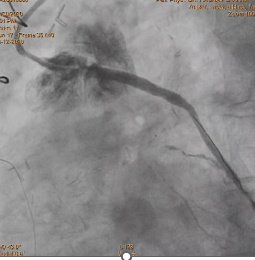

· TVD-Diffused disease- LAD, LCX& RCA

- SVG TO OM DLCX MID SEGMENT 90% Distally Near ANASTOMOSIS 80%

Planned SVG Stenting -OM and Distal LCX ,

stent was deployed in OM and LCX

After deployment observed Perforation of SVG-OM Distal LCX post Stenting.

Used two covered stent to cover perforation OM and LCX .

After using covered stent perforation was sealed and TIMI 3 flow achieved